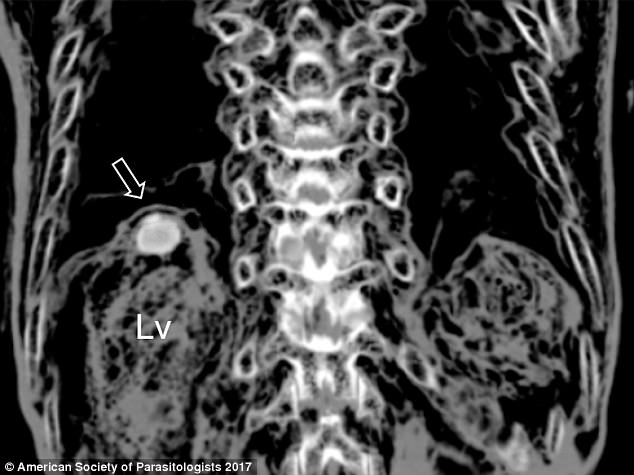

Dấu vết của trứng sán trong lá gan xác ướp.

Trong quá trình chụp cắt lớp (CT), các nhà nghiên cứu đã nhận ra dấu vết bất thường trong lá gan của xác ướp. Các nhà nghiên cứu Hàn Quốc đã trực tiếp khám nghiệm xác ướp để tìm hiểu vấn đề rõ hơn.

Đó là lúc mà các nhà nghiên cứu phát hiện ra trứng của loài ký sinh trùng mang tên Paragonimus westermani, hay còn gọi là sán lá phổi.